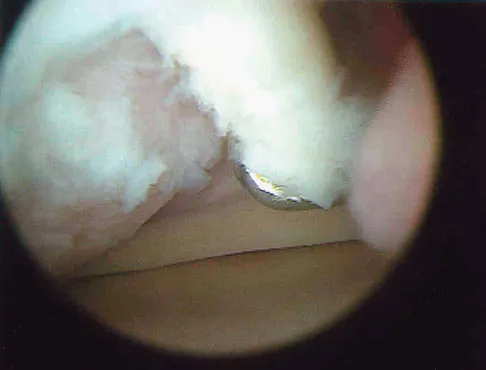

Management of a grade IV osteochondritis dissecans lesion of the capitellum should consist of